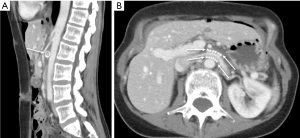

Cross-sectional imaging with CT and MRI relies on vessel diameter and, to a lesser extent, SMA angle to identify pathologic narrowing of the LRV. A normal aorta-to-SMA angle is between 45 and 90 degrees. An angle of 35 degrees in sagittal dimension suggests NCS (37) (Figure 5A). In the axial plane, a characteristic “beak” sign with abrupt narrowing of the LRV at the SMA is reported to have a sensitivity of 91.7% and specificity of 88.9% (38). As normal absolute values vary by patient, studies have focused on the ratio of diameters of the LRV at the renal hilum as compared to those at the narrowed AM segment. On CT, a hilar-to-AM diameter ratio of ≥4.9 has a 66.7% sensitivity and 100% specificity for NCS (Figure 5B) (2). A separate study demonstrated a 91% sensitivity and 91% specificity for NCS with a “compression ratio” of 2.25, which was described as adequate to raise suspicion for the disease, in the context of symptoms (39). Predictably, higher compression ratios were associated with more symptoms.